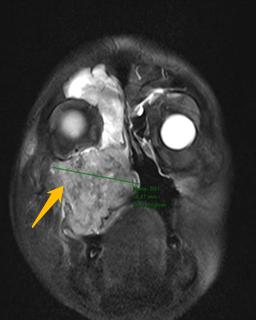

磁共振(MRI)检查结果图示而这次因身体不适来院就诊的结果,对J先生而言犹如晴天霹雳。磁共振显示右侧上颌窦充满了肿瘤组织,肿瘤还向周围结构扩展,侵犯了筛窦、眼眶底部、牙槽、硬腭、软腭、翼腭窝、面颊部皮肤,已丧失了彻底手术切除的机会。

将病情和治疗新进展与患者及家属充分沟通后,医生和患者及家属达成了一致的想法,愿意先采用化疗联合免疫治疗的方法一试,其间密切跟踪右侧上颌窦肿瘤退缩情况。患者的充分信任和医生的努力换来了可喜的结果:一个疗程治疗后,患者的右半边头痛即得到了缓解,面部肿胀开始消退。两个疗程后行鼻腔鼻窦磁共振检查,肿瘤完全退缩。